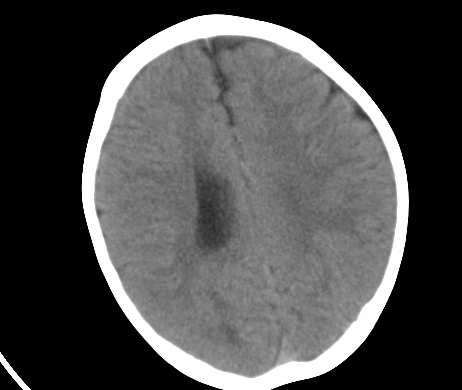

标题: PED1850:男 2岁 头部外伤1天,有事吗?

男 2岁 头部外伤1天,有事吗?科里意见不一 骨窗 没事,未上传